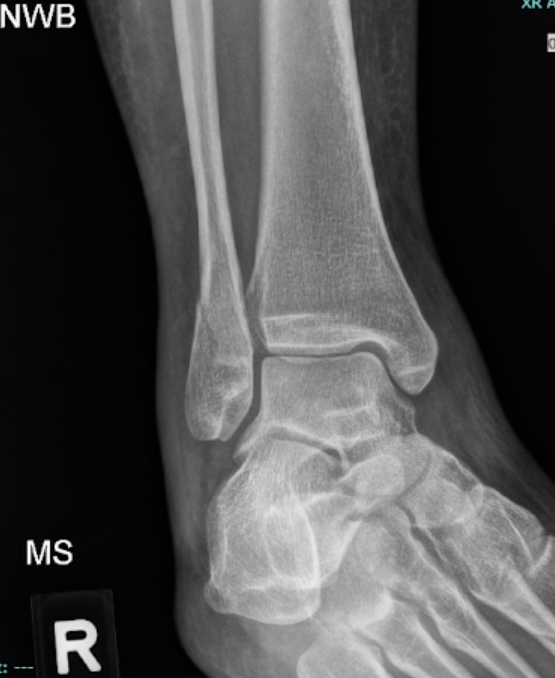

A 21-year-old female presents to the emergency room after falling from dancing on a table and injuring her right ankle. She is in severe pain and unable to bear weight comfortably with swelling and tenderness along the lateral malleolus. X-rays are taken and shown above.